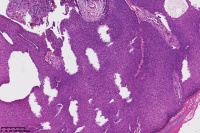

汗孔瘤?

性别

女

年龄

50岁

足底丘疹

汗孔瘤。